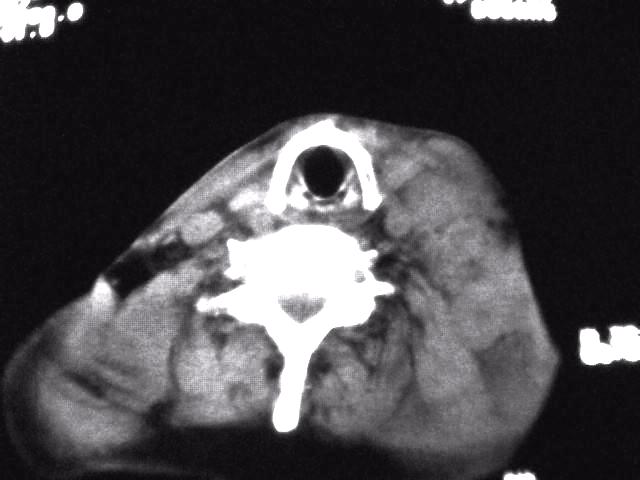

颈部层厚10mm间距10mm连续扫描及增强扫描共24层示:左侧下颈部胸锁乳突肌内侧区域内可见多发软组织结节,密度不均,内可见斑片状低密度区,大小不等,部分融合成块,左侧融合成一块者大约9.0x5.4,与周围肌肉、血管等结构界面不清,骨质未见明显浸润影。左侧锁骨下可见多个软组织结节,与周围界限尚清,左侧锁骨上窝内可见一大软组织肿物,大小约4.7x3.7cm,内密度欠均匀中心可见低密度区。

考虑:左侧颈部及双侧锁骨下多发淋巴结肿。非何杰金氏淋巴瘤可能性大,建议进一步检查。